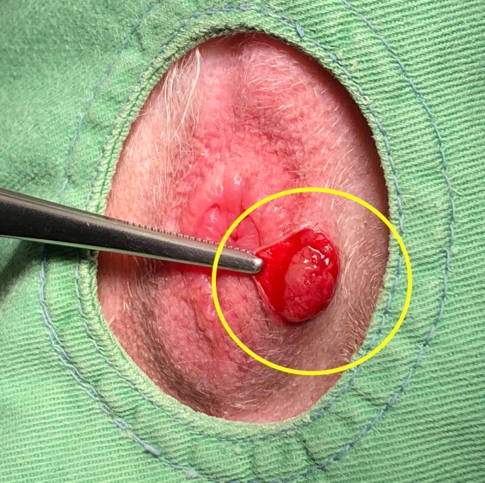

口腔内腫瘍

涎が増えたり、顔の腫れ、鼻からの出血、口臭、ご飯を食べることが困難になったり、口を開けた際に痛がるような症状を示します。

犬において多く認められる腫瘍は悪性メラノーマ、扁平上皮癌、繊維肉腫があります。

猫では扁平上皮癌が最も多い口腔内腫瘍です。

局所的な口腔内腫瘍では、外科的切除が最も多く使用される治療法であり、手術の方法は腫瘍の種類や位置によっても異なります。